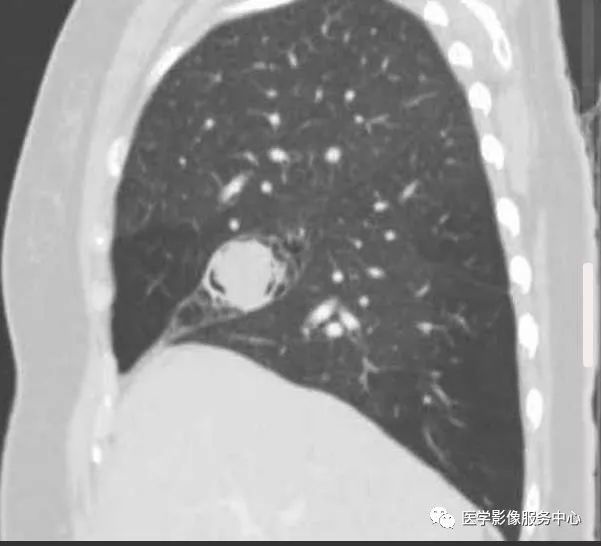

CT:右肺中叶见一个球形软组织密度影,周围见空气新月征

(1)致密阴影在空洞内随体位的改变而移动。在直立的胸部x线片,空气新月征位于致密阴影上;然而,在患者仰卧的CT图像上,空气新月征位于致密阴影前。

CT:初为肺部局限性炎症,表现为斑片状模糊阴影,继发周围炎症吸收,表现为团块状或结节状阴影,周围环以浅淡的磨玻璃样的晕,当肺组织液化,坏死物咳出后,则表现为:新月状的空气所包绕的一致密阴影,该致密阴影边缘光整,密度较均匀,增强无强化,且致密阴影在空洞内随体位的改变而移动。